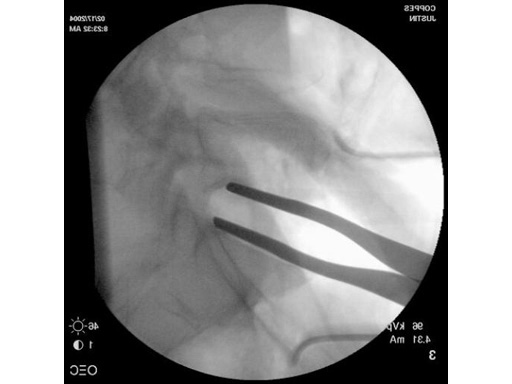

With the introduction of the SynFrame Standard Access and Retractor System, anterior mini-open procedures and less-invasive spine surgery became attainable for many surgeons. The SynFrame Standard Access and Retractor System enables small incisions and significantly reduces tissue damage and blood loss. In anterior lumbar procedures, both fusion and disc arthroplasty, improved intraoperative fluoroscopic visibility is needed. In disc arthroplasty good visualization is especially important. The radiolucent retractor blades offer surgeons a wider range of options for patients with excessive soft tissue and varying patient anatomy and provides improved fluoroscopic visualization. They are available in 80200 mm lengths in the standard 25 mm width and wide 50 mm width. The black surface coating also helps to reduce glare from the instruments during surgery.